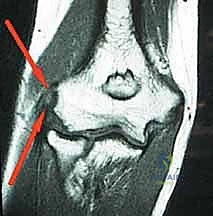

* الأشعة السينية (X-rays): لاستبعاد وجود التهاب مفاصل (خشونة) أو تكلسات عظمية.

* الرنين المغناطيسي (MRI): يُطلب في الحالات المزمنة التي لم تستجب للعلاج، لتحديد حجم التمزق في الوتر، واستبعاد مشاكل أخرى مثل انضغاط العصب الكعبري.

* الموجات فوق الصوتية (Ultrasound): طريقة ممتازة وسريعة لتقييم سماكة الوتر ووجود تمزقات مجهرية.

* إثبات وجود تمزق كبير في وتر (ECRB) عبر أشعة الرنين المغناطيسي.